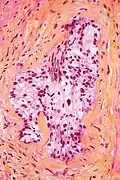

HPS stain

Micrograph of a HPS stained section demonstrating perineural spread of prostate adenocarcinoma.

In histology, the HPS stain, or hematoxylin phloxine saffron stain, is a way of marking tissues.

HPS is similar to H&E, the standard bearer in histology. However, it differentiates between the most common connective tissue (collagen) and muscle and cytoplasm by staining the former yellow and the latter two pink,[1] unlike an H&E stain, which stains all three pink.